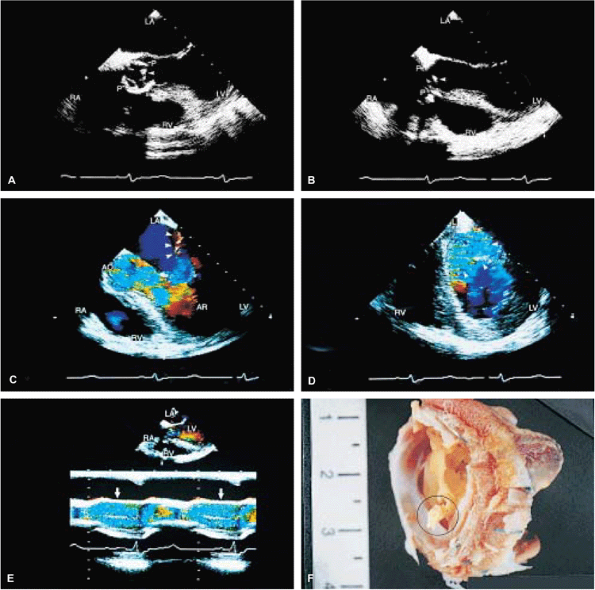

FIGURE 5.1. St. Jude mitral prosthesis: normal. The mitral prosthesis (MP) is seen in the closed (A) and open (B) positions. A. Prosthetic reverberations or artifacts (arrows) that clutter the left ventricle (LV). B. The two leaflets (1 and 2) of the prosthesis in the open position together with the reverberations. C. Aliased diastolic inflow into the LV is seen with a small region of flow acceleration. D–G. Two to three small jets of mitral regurgitation (MR; arrows) are shown. These are normal findings. Usually, these jets are narrow and do not show significant turbulence but may extend deep into the left atrium (LA). G. illustrates the norm (not pansystolic). H. Small linear echoes are normally seen on both the atrial and ventricular aspects of the prosthesis and represent suture material. I, J. Immediately postsurgery, although the patient is still on partial bypass, one leaflet of the prosthesis (P) may intermittently fail to open. This should not be mistaken for dysfunction. When cardiac output improves, normal opening of both leaflets occurs consistently. RV, right ventricle; RA, right atrium. |